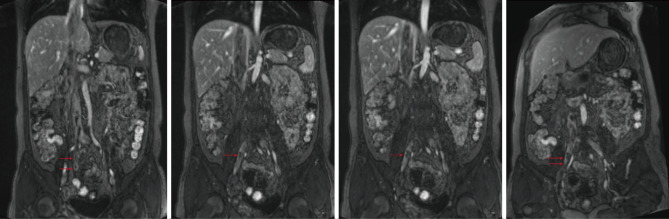

Case description: We report a case of retrogradely growing IVL, originating in the uterus and extending along the venous system to the right heart. At the same time, this leiomyomatosis retrogrades into the right external iliac vein. A 48-year-old woman with a mass in the IVC was admitted to Wuhan Union Hospital. She had undergone a hysterectomy for fibroids 2 years previously. Computed tomography venography and three-dimensional reconstruction revealed filling defects in the IVC, right internal and external iliac veins, right common iliac vein, right renal vein, and right atrium. After a multidisciplinary consultation, IVC leiomyomatosis was considered, and surgical treatment was performed.

Conclusions: We report a case of retrogradely growing IVL. It originates in the uterus, extends along the venous system to the right internal iliac vein, and grows retrogradely into the external iliac vein. This is a new growth path that has rarely been mentioned.